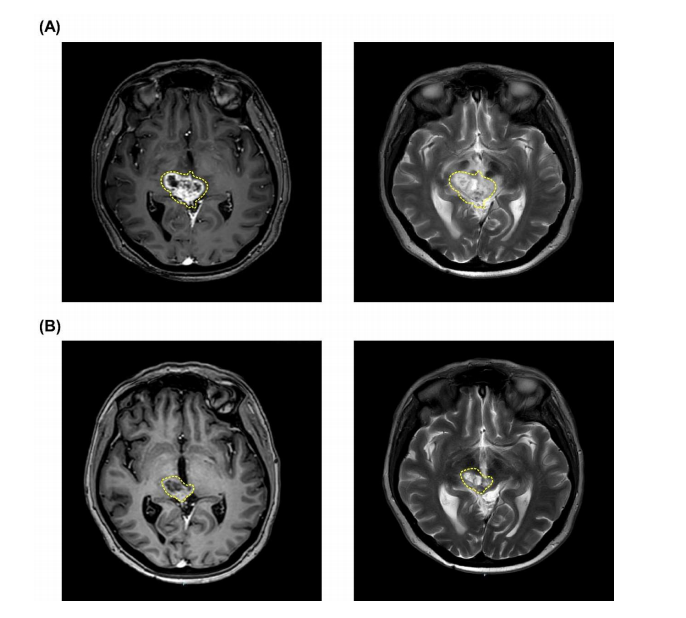

18F-BPA-PET檢查顯示T/N比為3.83?;颊咴?021年11月、12月共接受兩次BNCT治療。第一次和第二次BNCT的平均腫瘤劑量為10.95 Gy-E和9.68 Gy-E。在第一次和第二次BNCT治療期間,血硼濃度分別保持在22.85ppm和26.95ppm?;颊咴趦纱蜝NCT治療后獲得了CR(圖3),未觀察到嚴(yán)重急性或晚期毒性反應(yīng)。截止到交稿時(shí),患者身體狀況良好,沒有復(fù)發(fā)和進(jìn)展。

圖3:腫瘤縮小的MRI圖像,經(jīng)過兩次BNCT,患者達(dá)到CR,黃色虛線處表示腫瘤。